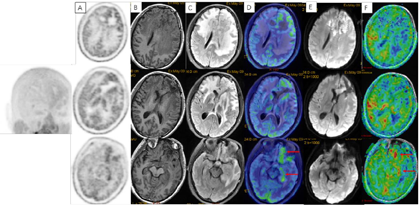

术后3周患者就诊于头颈肿瘤放化疗科,专科查体:左眼睑下垂,神清,言语清晰,伸舌居中,双侧瞳孔等大等圆,对光反射存在,四肢感觉活动可,肌力肌张力正常。2017年7月MR(图4)示左额叶术后改变伴出血,病灶内侧部分考虑肿瘤残留可能。为了更好地评估术后残留病变范围和制定放疗计划,患者行11C-MET PET/CT检查(图5A-D),结果示左侧脑室前角旁-左侧基底节区团块状稍高密度影,蛋氨酸代谢异常增高,考虑肿瘤残留。参照2016 ESTRO-ACROP指南[1],继发性胶质母细胞瘤放疗GTV靶区需包含术腔、T1增强上的强化区域及T2 FLAIR上的高信号区域,术后PET/CT显像所示的氨基酸代谢活跃病灶被包含在GTV之内(图5E)。患者于2017年7月始行左额叶病灶放疗(PTV 60Gy/30F,同步口服替莫唑胺化疗75mg/m2,qd)。结束后复查PET/CT(图5F-I)示病变范围明显缩小,代谢程度较前减低,左额叶少许病变存活,遂对残留病灶局部放疗加量(GTV如图5J,6Gy/3F)。放疗过程顺利,期间出现Ⅲ°白细胞减低,予以升白细胞治疗后好转出院。后于2017年10月起口服替莫唑胺辅助化疗(150~200mg/m2,d1-d5,q28d),期间规律复查。

2018年3月、6月MR复查发现病灶范围逐渐增大(图6),提示不除外复发可能。患者除了轻微头痛之外并无明显不适,临床考虑假性进展,予安维汀100mg治疗后症状好转。2018年8月复查11C-MET PET/MR显像未见明显代谢增高病灶,证实为假性进展(图7)。2018年11月复查未见明显肿瘤复发,2019年3月2日MRI复查(图8)再次提示病变增大,考虑肿瘤进展。2019年3月行PD-1单抗(拓益)治疗,治疗过程中患者出现行走不稳,1月后患者不慎跌倒,外院就诊行颅脑CT未见明显出血。期间发现患者肝功能异常,给予护肝治疗后好转。2019年5月复查PET/MR(图9)提示左侧额叶前下部、左侧海马区及左侧颞叶前部蛋氨酸代谢较前次增高,其中左侧海马及左额叶直回ASL灌注相对增高,考虑复发可能,免疫治疗后存活。遂停用免疫治疗,根据患者全基因组测序结果选择靶向药物安罗替尼治疗(主要针对VEGFR、PDGFR、FGFR、c-KIT多个靶点),2019年12月复查PET/MR(图10)提示病变活性受抑。电话随访得知患者因武汉疫情影响无法按期治疗和复查,后合并肺部感染,于2020年8月去世。